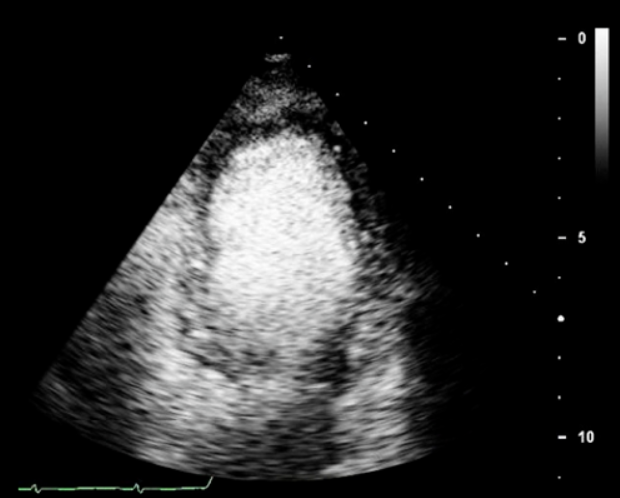

The Ultimate Ultrasound Enhancing Agents Quick Guide

Our quick guide provides in-depth insights into using ultrasound enhancing agents to elevate the quality and accuracy of your scans. Learn how to optimize your scanning techniques and deliver exceptional results for improved patient care.